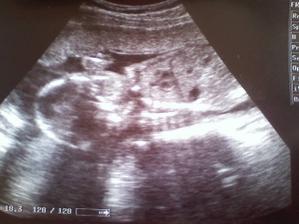

Náš prďolka

O letošních Vánocích už budeme pod stromečkem 3, teda alespoň doufáme, že půjde vše, tak jak má :o) Naše štěstíčko by se mělo na svět přijít podívat 8.12.2010 a už teď se na něj s tatínkem moc těšíme.